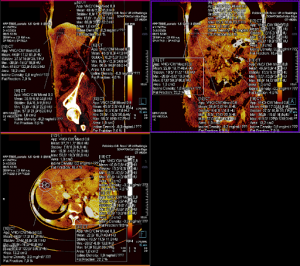

E' stata adoperata sempre la stessa macchina dotata di detettori a 128 strati (TC SOMATOM Definition Edge di Siemens Healthcare, Erlangen, Germania) con una risoluzione spaziale di 0,30 mm, dotata di tecnologia Twin-Beam. L'analisi delle immagini a doppia energia è stata eseguito tramite il software syngoCT Workplace VB20 di Siemens Healthcare GmbH (Erlangen, Germania) con l’applicativo “Liver VNC Application Class” per l'analisi delle scansioni TC eseguite in fase portale TBDE. Sulle immagini VNC, un radiologo esperto ha tracciato da 3 a 6 regions of interest (ROI) per ciascuna lesione (superiore, inferiore ed in base all'estensione da 1 a 4 ROI centrali) con area di 1 cm^2, una ROI centrale più estesa che comprendesse 5 mm di parenchima epatico non-ablato tracciato sullo stesso piano della ROI centrale di 1 cm^2 (FIGURA 2-3-4-5). Nel tracciare le ROI si è posta la massima attenzione nell’evitare strutture peri-lesionali e i vasi sanguigni. Per ogni ROI tracciata è stato estrapolato il valore quantitativo della densità dello iodio in mg/dl considerando anche valori negativi (ovvero privi di impregnazione di mezzo di contrasto). Allo stesso radiologo è stato poi richiesto di compilare in cieco, una scheda qualitativa che decretasse se il trattamento effettuato fosse "completo" o "incompleto" nelle TC analizzate (TABELLA 1).

FIGURA 4. Esempio di analisi VNC in tre diverse proiezioni: sagittale (in alto a sinistra), coronale (in alto a destra) e assiale (in basso). Ben visibili i le informazioni estratte da tutte le ROI tracciate.